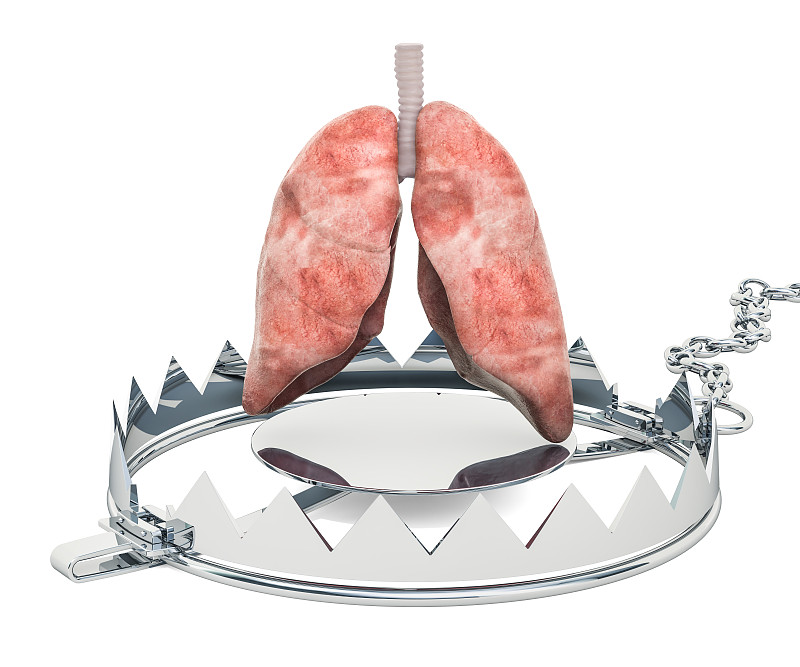

肺结核。详情